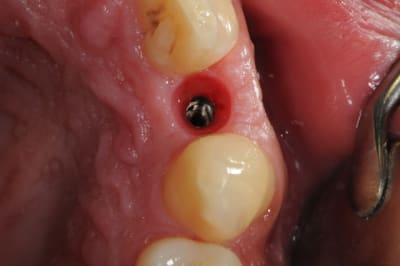

je reviens sur ce cas que j'ai un peu délaissé...

-cicatrisation

-mise en place vis de cica petit diamètre

-ensuite on augmente le diamètre en conservant et en gonflant les tissus gingivaux